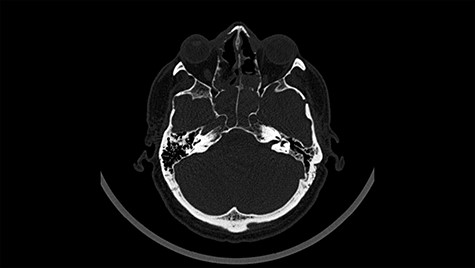

A 49-year-old patient presented after surgical treatment of nasal polyps, with headache and consciousness disorders (behavioral changes, drowsiness and allophenic orientation disorders). Computed tomography (CT) scan showed (Fig. 1) a presence of blood in fluid spaces, widening of the ventricular system (without active hydrocephalus features) and presence of air in the frontal horns of the lateral ventricles and features of cerebral edema. Due to the subarachnoid hemorrhage, an angio-CT and CT scan was performed, showing no vascular malformation. The patient's condition deteriorated with a drop in Glasgow Coma Scale (GCS) to 9, strongly expressed meningeal syndrome and a fever of > 38°C. In the performed cerebrospinal fluid examination a typical picture for bacterial infection, cultures negative. Treatment was implemented in accordance with the neuro-infections algorithm. Clinical and laboratory features of neuroinfections have withdrawn. The neurological condition of the patient improved to GCS 11. Control head CT (Fig. 2) showed enlargement of the ventricular system with cerebrospinal fluid transudation.

Head CT after polypectomy—presence of blood in fluid spaces, widening of the ventricular system, presence of air in the frontal horns of the lateral ventricles, features of cerebral edema. (Department of Neurosurgery Neurotraumatology and Pediatric Surgery own material).

In described case, a head CT scan after polypectomy confirmed the subarachnoid hemorrhage (Fig. 1). In addition, the presence of air in the ventricular system was visible, and presence of defects of the upper left orbital wall and ethmoid on both sides (Fig. 3). In the CT scan sphenoid sinus, frontal and ethmoidal sinuses on both sides and right maxillary sinus airless, filled with blood and soft tissue. The changes also concerned the lateral part of the left maxillary sinus (Fig. 4).